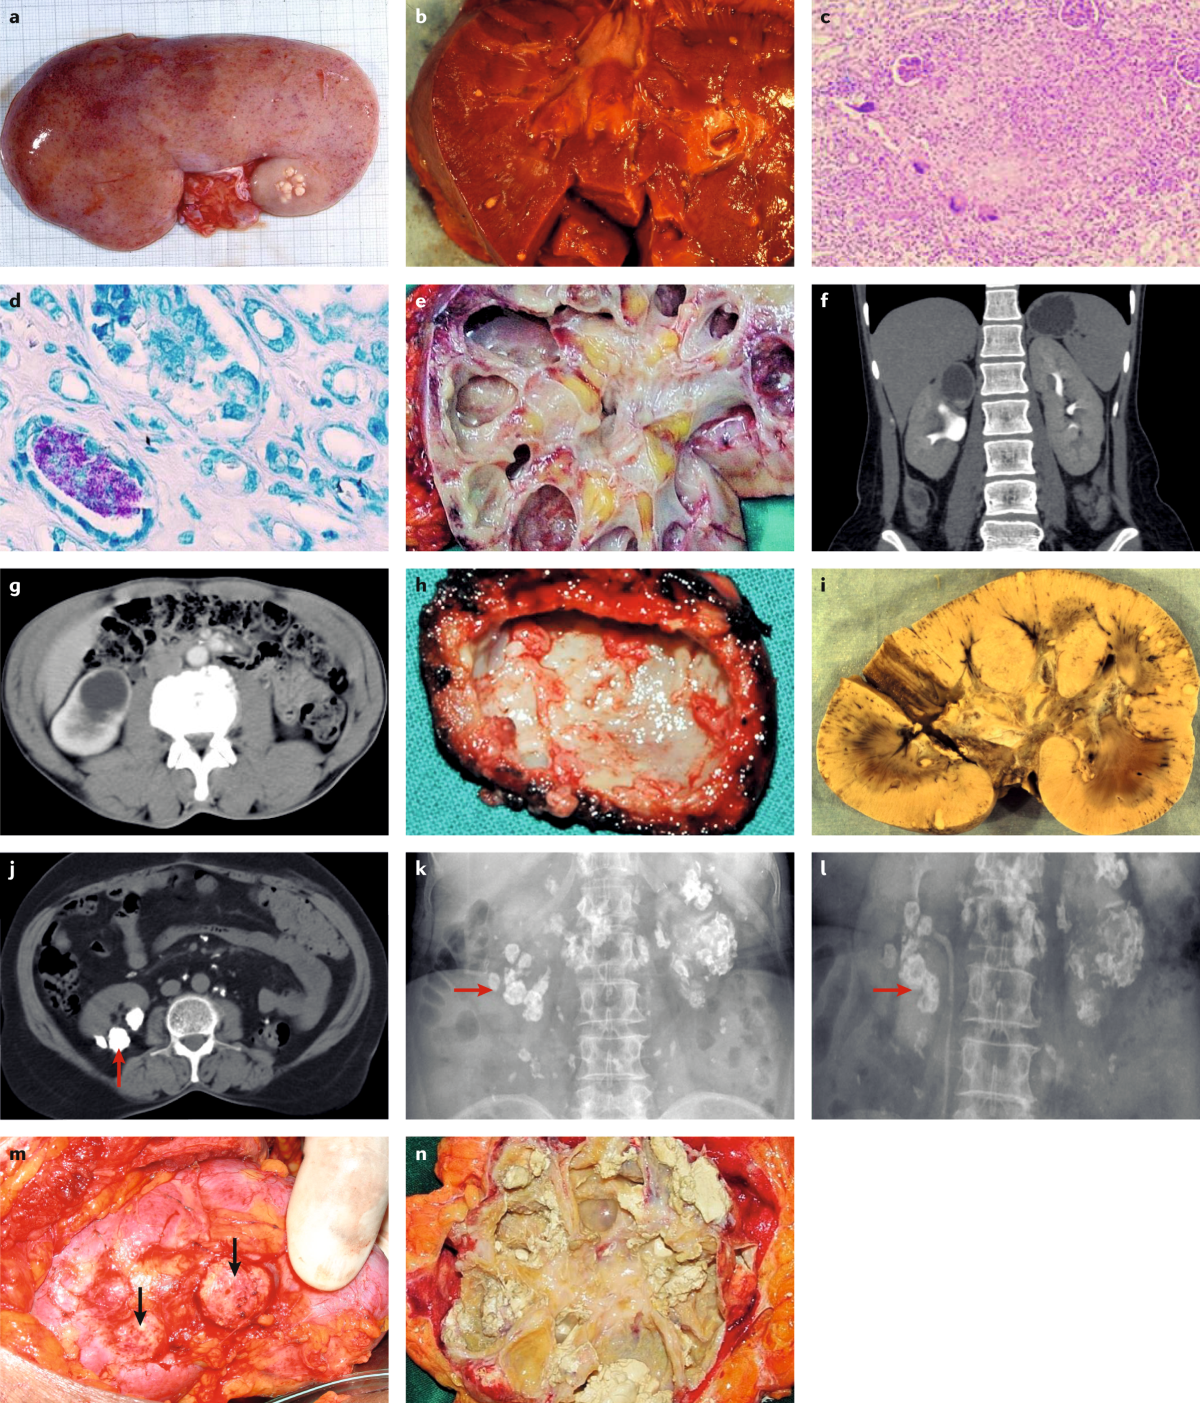

Urogenital tuberculosis — epidemiology, pathogenesis and clinical features | Nature Reviews Urology